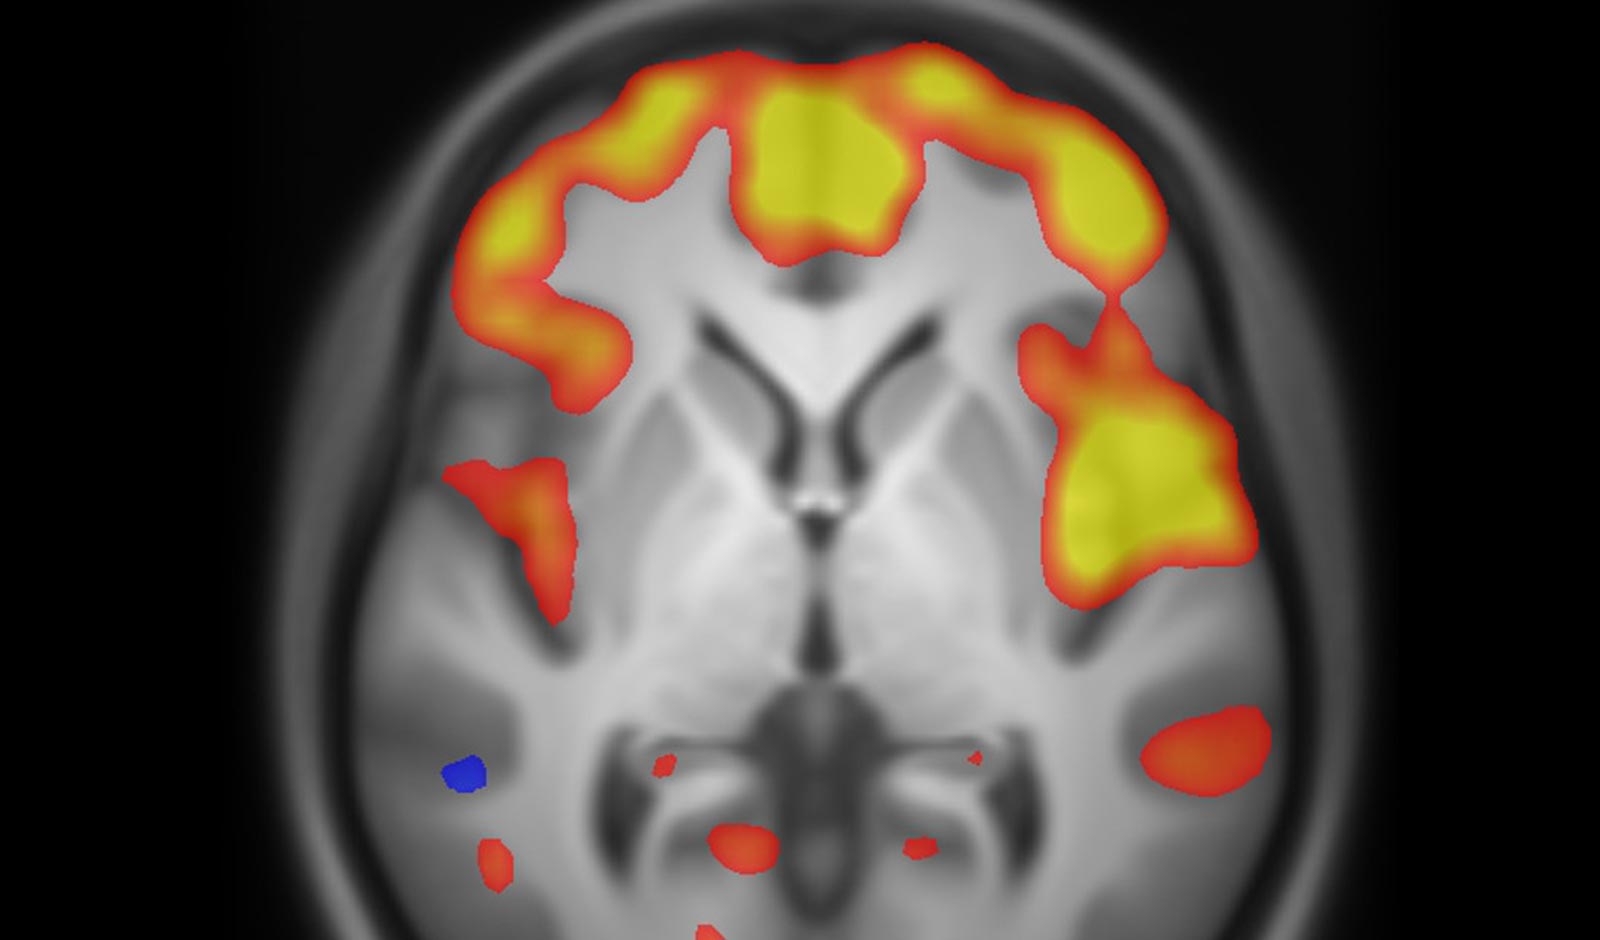

Die Forschung der Arbeitsgruppe konzentriert sich auf die Untersuchung geschlechtsabhängier Aspekte von Gehirnfunktionen unter Einsatz moderner neurobildgebender Methoden. Ziel ist es, ein besseres Verständnis der neurobiologischen Grundlagen geschlechtsbezogener Unterschiede zu gewinnen und deren Relevanz für differenzierte diagnostische und therapeutische Verfahren zu analysieren. Ein weiterer Schwerpunkt liegt auf geschlechtersensibler Medizin sowie häuslicher Gewalt. Die Arbeitsgruppe hat zudem eine Europäische Trainingsplatform zum Thema häusliche Gewalt für den Medizinsektor erstellt, die dazu dient, das Wissen und die Kompetenzen der Fachkräfte in diesem Bereich zu erweitern und zu vertiefen.